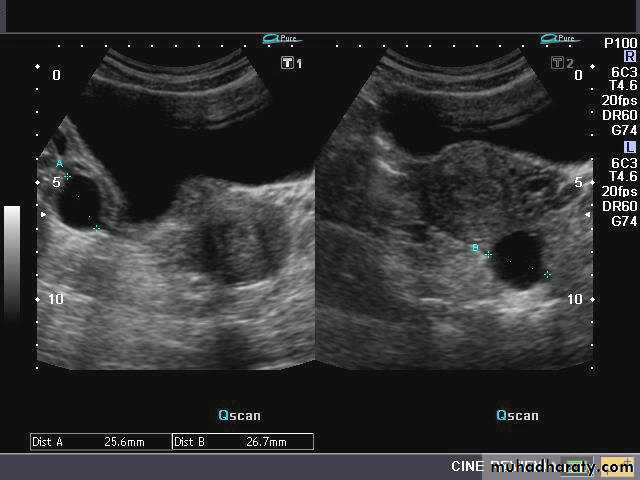

Ovarian hyperstimulation syndrome (OHSS):

Ultrasonography in Gynaecology

This young adult female patient was examined to evaluate the uterus and ovaries. She was under treatment for infertility and was using gonadotropins. Ultrasound images of the ovaries show grossly enlarged ovaries with large cysts (measuring 2.6 to 3 cms.) in both ovaries. These ultrasound findings are diagnostic of OHSS or ovarian hyperstimulation syndrome.

• Ovarian hyperstimulation syndrome (OHSS):

The ultrasound image again show hyperstimulated ovaries. Both ovaries are grossly enlarged and cystic.